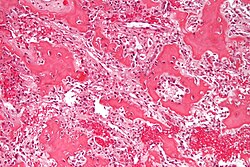

Microscopic

Features:

- Fibrosis.

- +/-Giant cells with round to oval nuclei and nucleoli.[10]

- Bone unaffected by tumour - increased numbers of the following:

- Multinucleated cells (osteoclasts).

- Mononuclear cells around the bony trabeculae (osteoblasts).

DDx:

- Giant cell tumour of bone and other giant cell lesions.

- Brown tumour - intermed mag.jpg

Brown tumour - intermed. mag. (WC)